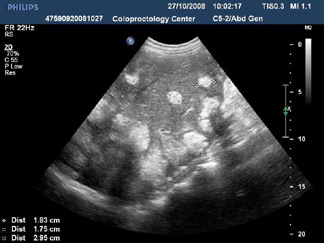

Трансабдоминальное 2D ультразвуковое исследование печени. Множественные очаговые образования.